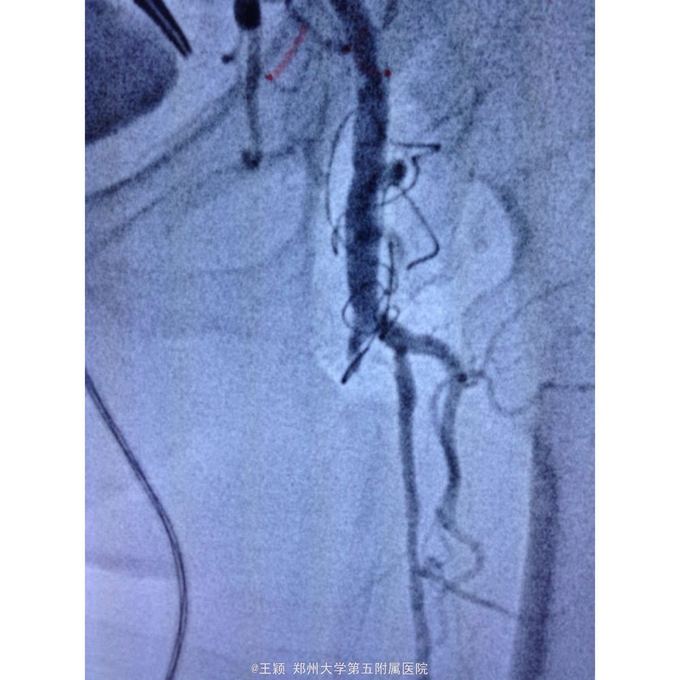

诊断为:下肢动脉硬化闭塞症D级并左足坏死 处理:85岁高龄患者,拟局麻翻山,先行处理左侧,术中患者不能配合,且造影发现左侧股总动脉远端近分叉处存在重度狭窄,钙化明显,即使顺利开通闭塞段,股总动脉的处理非常棘手,单纯球扩效果不佳,放置支架势必遮挡股深动脉,一旦出现问题,再次处理非常麻烦,综合考虑后改为全麻,局部切开后,剥脱股总及股浅动脉近段斑块,股浅动脉远端未进一步处理,术后造影,股总动脉远端狭窄解除,股深动脉显影较前改善,术后下肢皮温皮色均好转!

术后下肢皮温皮色均好转